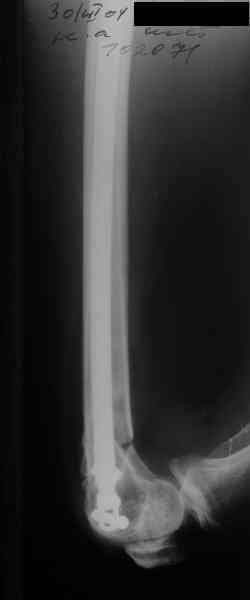

Re: Перелом диафиза и мыщелка бедра

I> Насчет снимка Вами представленного - смотрится оч красиво, еще бы на

I> функцию узнать...

В приложении функциональные снимки в 3 мес. и в 1 год.